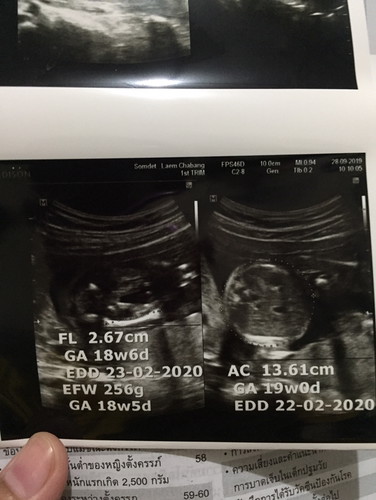

มีความสงสัยนะคะแม่ๆ พึ่งไปซาวน์ดูอวัยวะน้องมา อายุครรภ์จริง 21w แต่ในใบอันตราซาวน์พึ่ง 18w เราจะยึดน้ำหนักน้องที่อันไหนคะพอดีออกจากห้องตรวจแล้วใบอันตราซาวน์ตามมาทีหลังเลยไม่ได้ถามคุณหมอ แต่โดยรวมคุณหมอว่าปกติดี

ส่วนใหญ่ยึดตามใบซาวด์ค่ะ เพราะร่างกายคนเราไข่ตกช้าเร็วไม่เท่ากัน บ้านนี้นับกำหนดคลอดตามปจด.กับอัลตร้าซาวด์ก็ไม่ตรงกัน